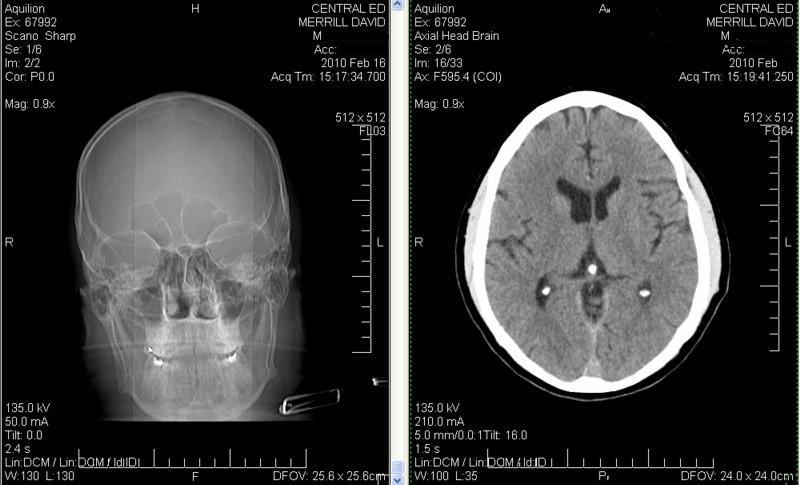

It looks to the layman me, like I have three pineal glands? After studying the links though, I think the other two calcified organs are my amygdali.

Click image for larger version

Name:	CT Smiley Face s.jpg

Views:	1

Size:	98.7 KB

ID:	46945

See the smile? That's where I have sex.